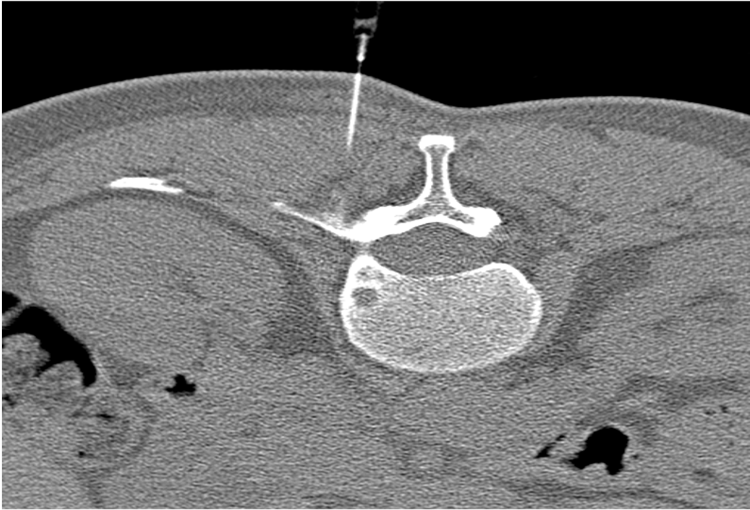

120 kV / 30 mAs / 1mm

Before FBP (Noise 150) VS After ClariCT.AI (Noise 49) 67% Denoising